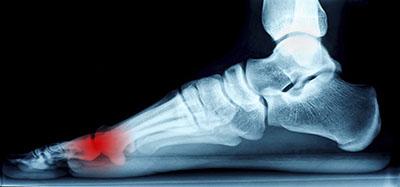

Ankle Pain

Ankle pain, while initially thought of as an issue for athletes, can affect anyone at anytime. Simple, everyday activities, such as walking or running on an uneven surface, have the possibility of causing serious harm to one’s ankle. That is, however, not to discount...